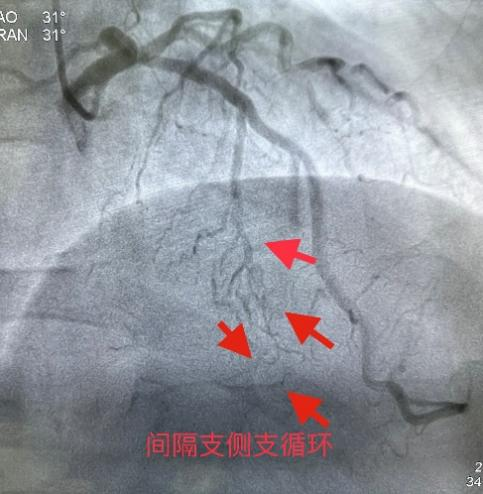

3月8日经过充分的术前准备,雷新军教授带领景林德博士和蔡安琪医生按照预定方案为患者实施了手术。冠脉造影示:RCA 2段慢性闭塞合并重度钙化,闭塞段长约30 mm,同向桥侧支供血使其远段显影(图3a);前降支散在斑块伴钙化,狭窄约25%-50%,并通过间隔支侧支循环向右冠逆向供血(图3b);回旋支11段狭窄约75%(图3c)。决定干预右冠:指引导管到位后在Guidezilla的支撑下,经Corsair微导管仔细操控GAIA 3rd穿过闭塞段进入远端血管真腔(图3d,e);然后通过微导管交换成旋磨导丝,使用1.5 mm Burr进行冠脉内斑块旋磨并抛光(图3f),造影见右冠恢复TIMI 3级前向血流,但2段残余狭窄最重处仍达90%(图3g);遂经导丝送入3.0*12 mm“Shockwave”冲击波球囊分段进行血管内碎石术:首先将压力充盈至4 atm后开始释放脉冲,松解钙化斑块,然后再将充盈压升至6 atm维持10秒,对靶病变进行低压球囊扩张成形(图3h);再次造影见右冠2段局限性夹层,闭塞段残余狭窄<10%(图3i),效果非常满意,遂由远及近衔接植入BioFreedom支架(图3j),历时约1小时手术成功,病人安返病房。

图3 经皮冠脉介入治疗